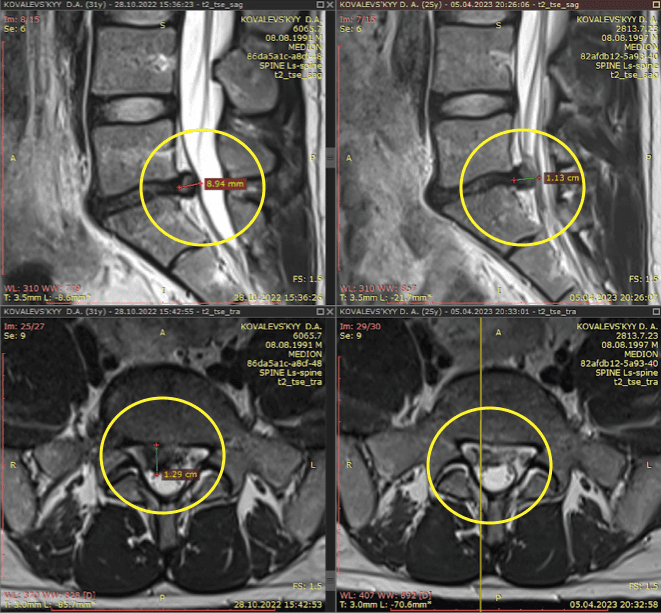

Метод лікування грижі шляхом стимуляції резорбції в Україні був впроваджений у 2020-2021 роках.  Алгоритм оцінки грижі на предмет резорбції, що використовується у клініках – є авторським, розроблений лікарем Боханом А.Ю.